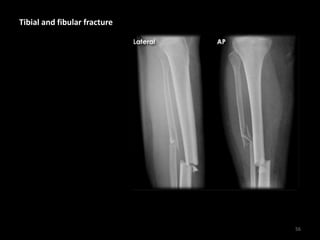

Tibial and fibular fracture

• Comminuted fractures

of the tibial and fibular

shafts with medial

displacement and

posterior angulation

• X-rays of the distal end

of the bones (not

shown) did not reveal

further injury

57